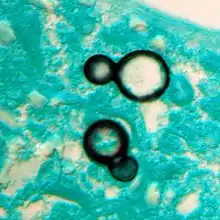

Once suspected, the diagnosis of blastomycosis can usually be confirmed by demonstration of the characteristic broad based budding organisms in sputum or tissues by KOH prep, cytology, or histology.[27] Tissue biopsy of skin or other organs may be required in order to diagnose extra-pulmonary disease. Blastomycosis is histologically associated with granulomatous nodules.

Granuloma with early suppuration. Fungal organisms difficult to recognize at this low magnification. Granuloma with early suppuration. Fungal organisms difficult to recognize at this low magnification.

Large yeast-like fungi seen within giant cells at arrows. Large yeast-like fungi seen within giant cells at arrows.

Large yeast-like fungi seen within giant cells at arrows. Budding yeasts in cytoplasm of giant cells at arrows. Broad-based budding and double contoured cell wall seen in the giant cell in the center is characteristic of Blastomyces dermatitidis. Large yeast-like fungi seen within giant cells at arrows. Budding yeasts in cytoplasm of giant cells at arrows. Broad-based budding and double contoured cell wall seen in the giant cell in the center is characteristic of Blastomyces dermatitidis.